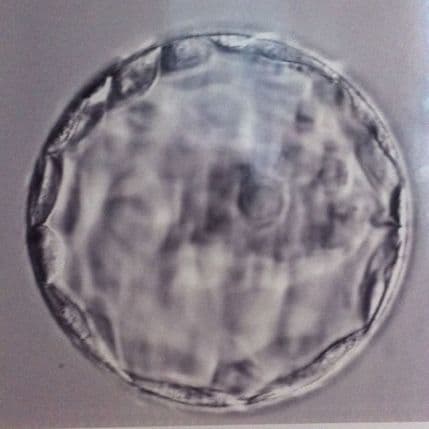

U terapeutskom kloniranju naučnici koriste elektricitet kako bi spojili odraslu ćeliju (obično ćeliju kože) sa jajnom ćelijom kojoj je uklonjen DNK. Jajna ćelija se za pet do šest dana razvija u embrion u obliku šuplje lopte.

Unutrašnje ćelije su "pluripotentne", odnosno imaju moć da postanu bilo koje ćelije ljudskog organizma. Kada bi takav embrion bio presađen u matericu, mogao bi se pretvoriti u klon donora DNK.

Ovog puta stvorena su dva zdrava embriona, po jedan od svakog donora starosti 35 i 75 godina.